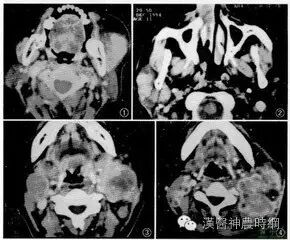

淋巴瘤是原发于淋巴结或淋巴组织的恶性肿瘤,临床以无痛性,进行性淋巴结肿大为主要表现。本病可发生于任何年龄,但发病年龄高峰在31—40岁,其中非霍奇金淋巴瘤高峰略往前移。男女之比为:2—3:1。一般认为,可能和基因突变,以及病毒及其他病原体感染、放射线、化学药物,合并自身免疫病等有关。

恶性淋巴瘤是具有相当异质性的一大类肿瘤,虽然好发于淋巴结,但是由于淋巴系统的分布特点,使得淋巴瘤属于全身性疾病,几乎可以侵犯到全身任何组织和器官。因此,恶性淋巴瘤的临床表现既具有一定的共同特点,同时按照不同的病理类型、受侵部位和范围又存在着很大的差异。

浅表淋巴结起病占多数,而HD又多于NHL,受累淋巴结以颈部为最多,其次是腋下,腹股沟,一般为无痛性,进行性肿大,中等硬度,早期可活动,晚期多发生粘连及多个肿大淋巴结融合成块,有些HD患者淋巴结肿大在某一时间可暂时停顿,甚至缩小,以致于误诊为淋巴结炎或淋巴结核。

深部淋巴结起病,以纵隔淋巴结为多见,肿大之淋巴结可压迫上腔静脉,引起上腔静脉综合征,也可压迫气管,食管,喉返神经而相应发生呼吸困难,吞咽困难和声音嘶哑等症状,纵隔NHL并发淋巴肉瘤细胞白血病者较多见,而青年妇女纵隔首发之HD多为结节硬化型,对治疗反应常不满意。

所谓的 " 淋巴腺肿大 ",是否即显示一个恶性癌症疾病,需要很小心去区分 , 因为一些比较没有危险性的疾病 ,比如淋巴结发炎或其它感染,亦可能造成淋巴腺的肿大 , 所以我们第一个在对付淋巴腺肿大时 ,必须仔细检查区分淋巴腺的大小,硬度,皮肤病变。并从病人的临床过程,淋巴结肿大的持续时间,大小,硬度的变化 及包括体重减轻,无缘无故发烧或夜间盗汗,还有皮肤发痒等症状去判断它究竟属于何种原因。